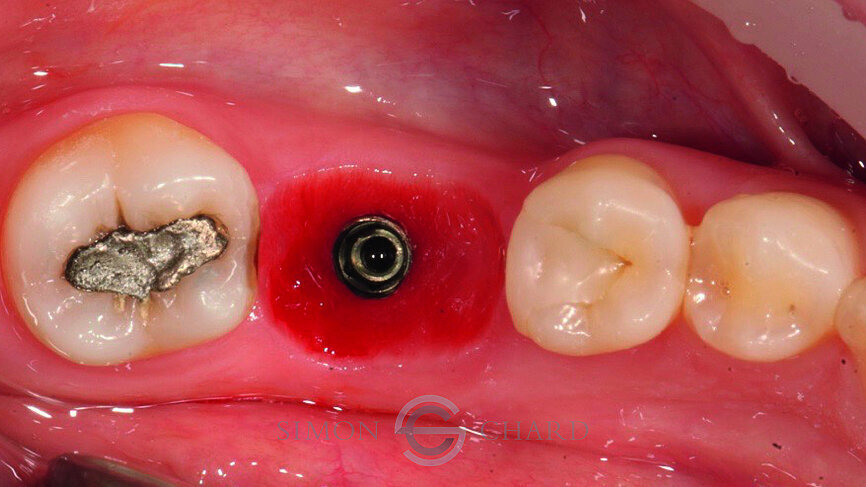

Following 3 months of integration, the patient attended the practice for the restoration of the implant with a definitive crown. During this period, the soft tissue had been given time to mature and a beautiful molar soft tissue profile had formed (Figs. 4 & 5).

Traditionally, capturing the detail of this soft tissue profile with analogue methods is complicated and time consuming; however, utilising a digital intraoral scan (CEREC Omnicam) a “gingival mask scan” can be taken to accurately replicate this soft tissue and use it to guide the subgingival emergence profile of the restoration (Fig. 6).

Following removal of the temporary crown, a TiBase was placed into the fixture head and a scan body used as a reference point for the scanning of the implant (Figs. 7 & 8).